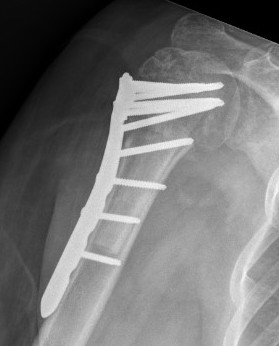

ORIF with locking plate

Apply plate

- lateral to biceps with single cortical screw in oblique hole

- check fluoroscopy - avoid having plate too high

- keep head out of varus to avoid cutout

- long inferomedial screws / kickstand screws

- locking screws

Plates

Long proximal humerus plates